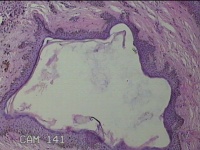

头部新生物

性别

男

年龄

31岁

临床诊断

纤维瘤

一般病史

头部皮肤起新生物1年。

标本名称

大体所见

灰白粉红色新生物1.7x0.5x0.3cm一个,表面糜烂,肿物表面有大量毛发。